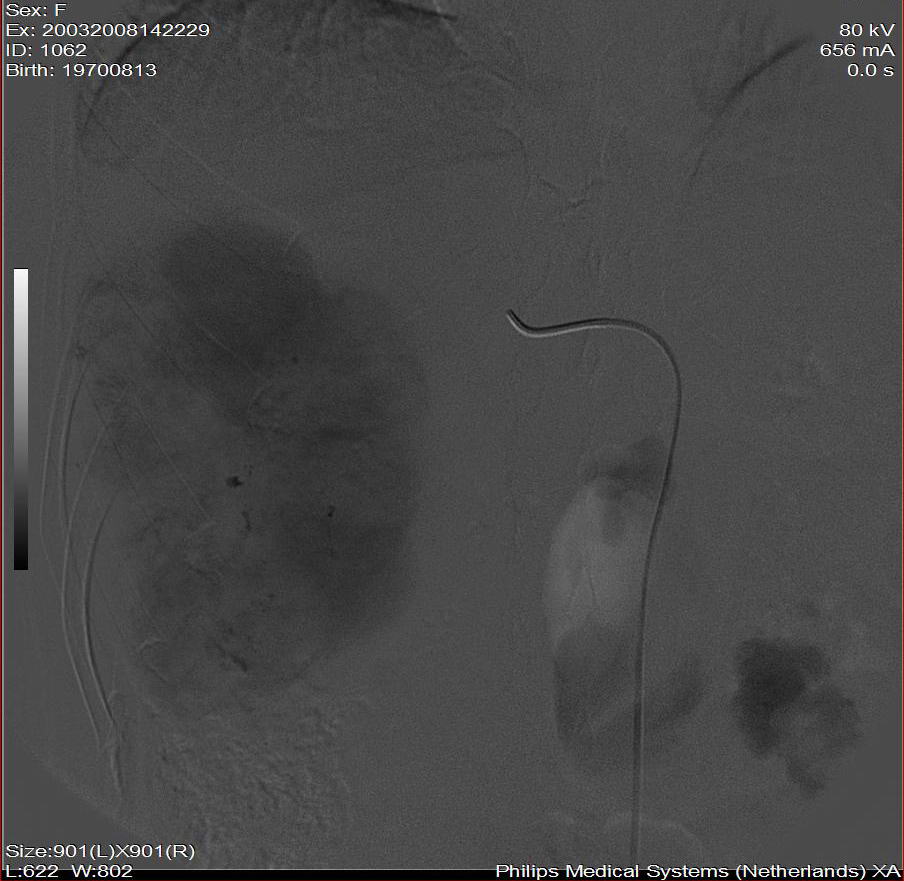

标题: DSA0138:F38Y,肝脏病变

第一次: